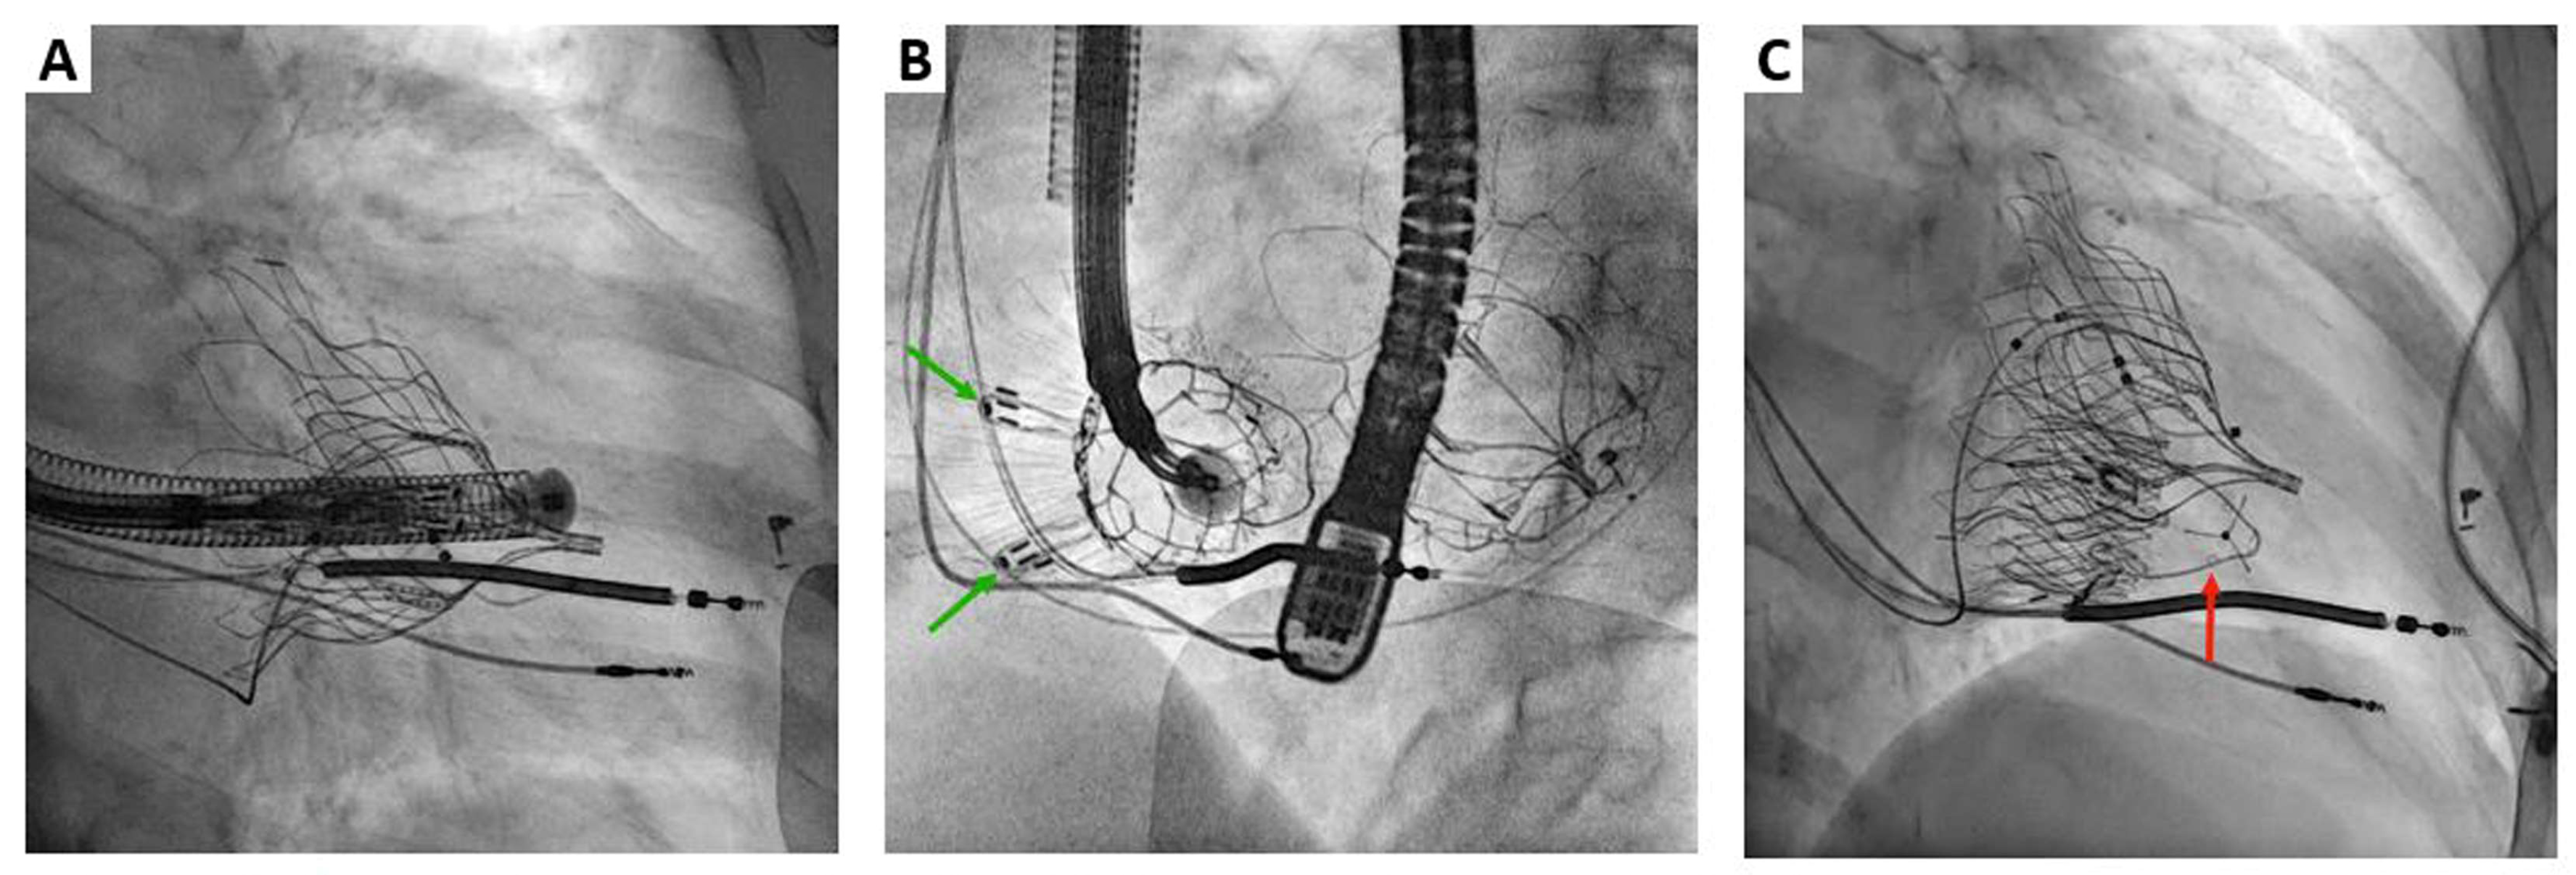

2. Cardiovalve Cases

3. Lux-Valve Plus Case